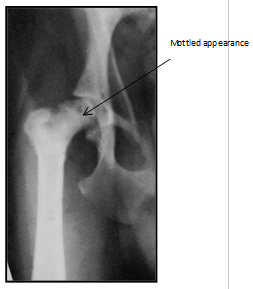

What is occuring here?

Usually unilateral –bilateral in 12-16.5% cases

Non-inflammatory aseptic necrosis of the femoral head and neck